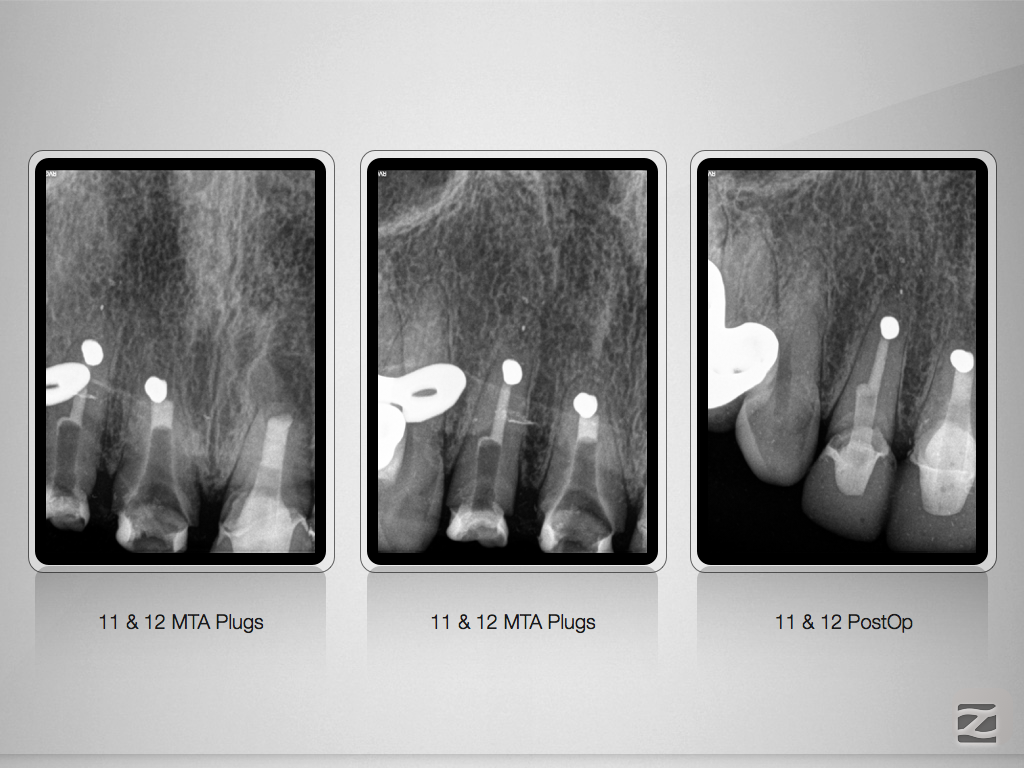

Viermal das Gleiche und doch nicht Dasselbe